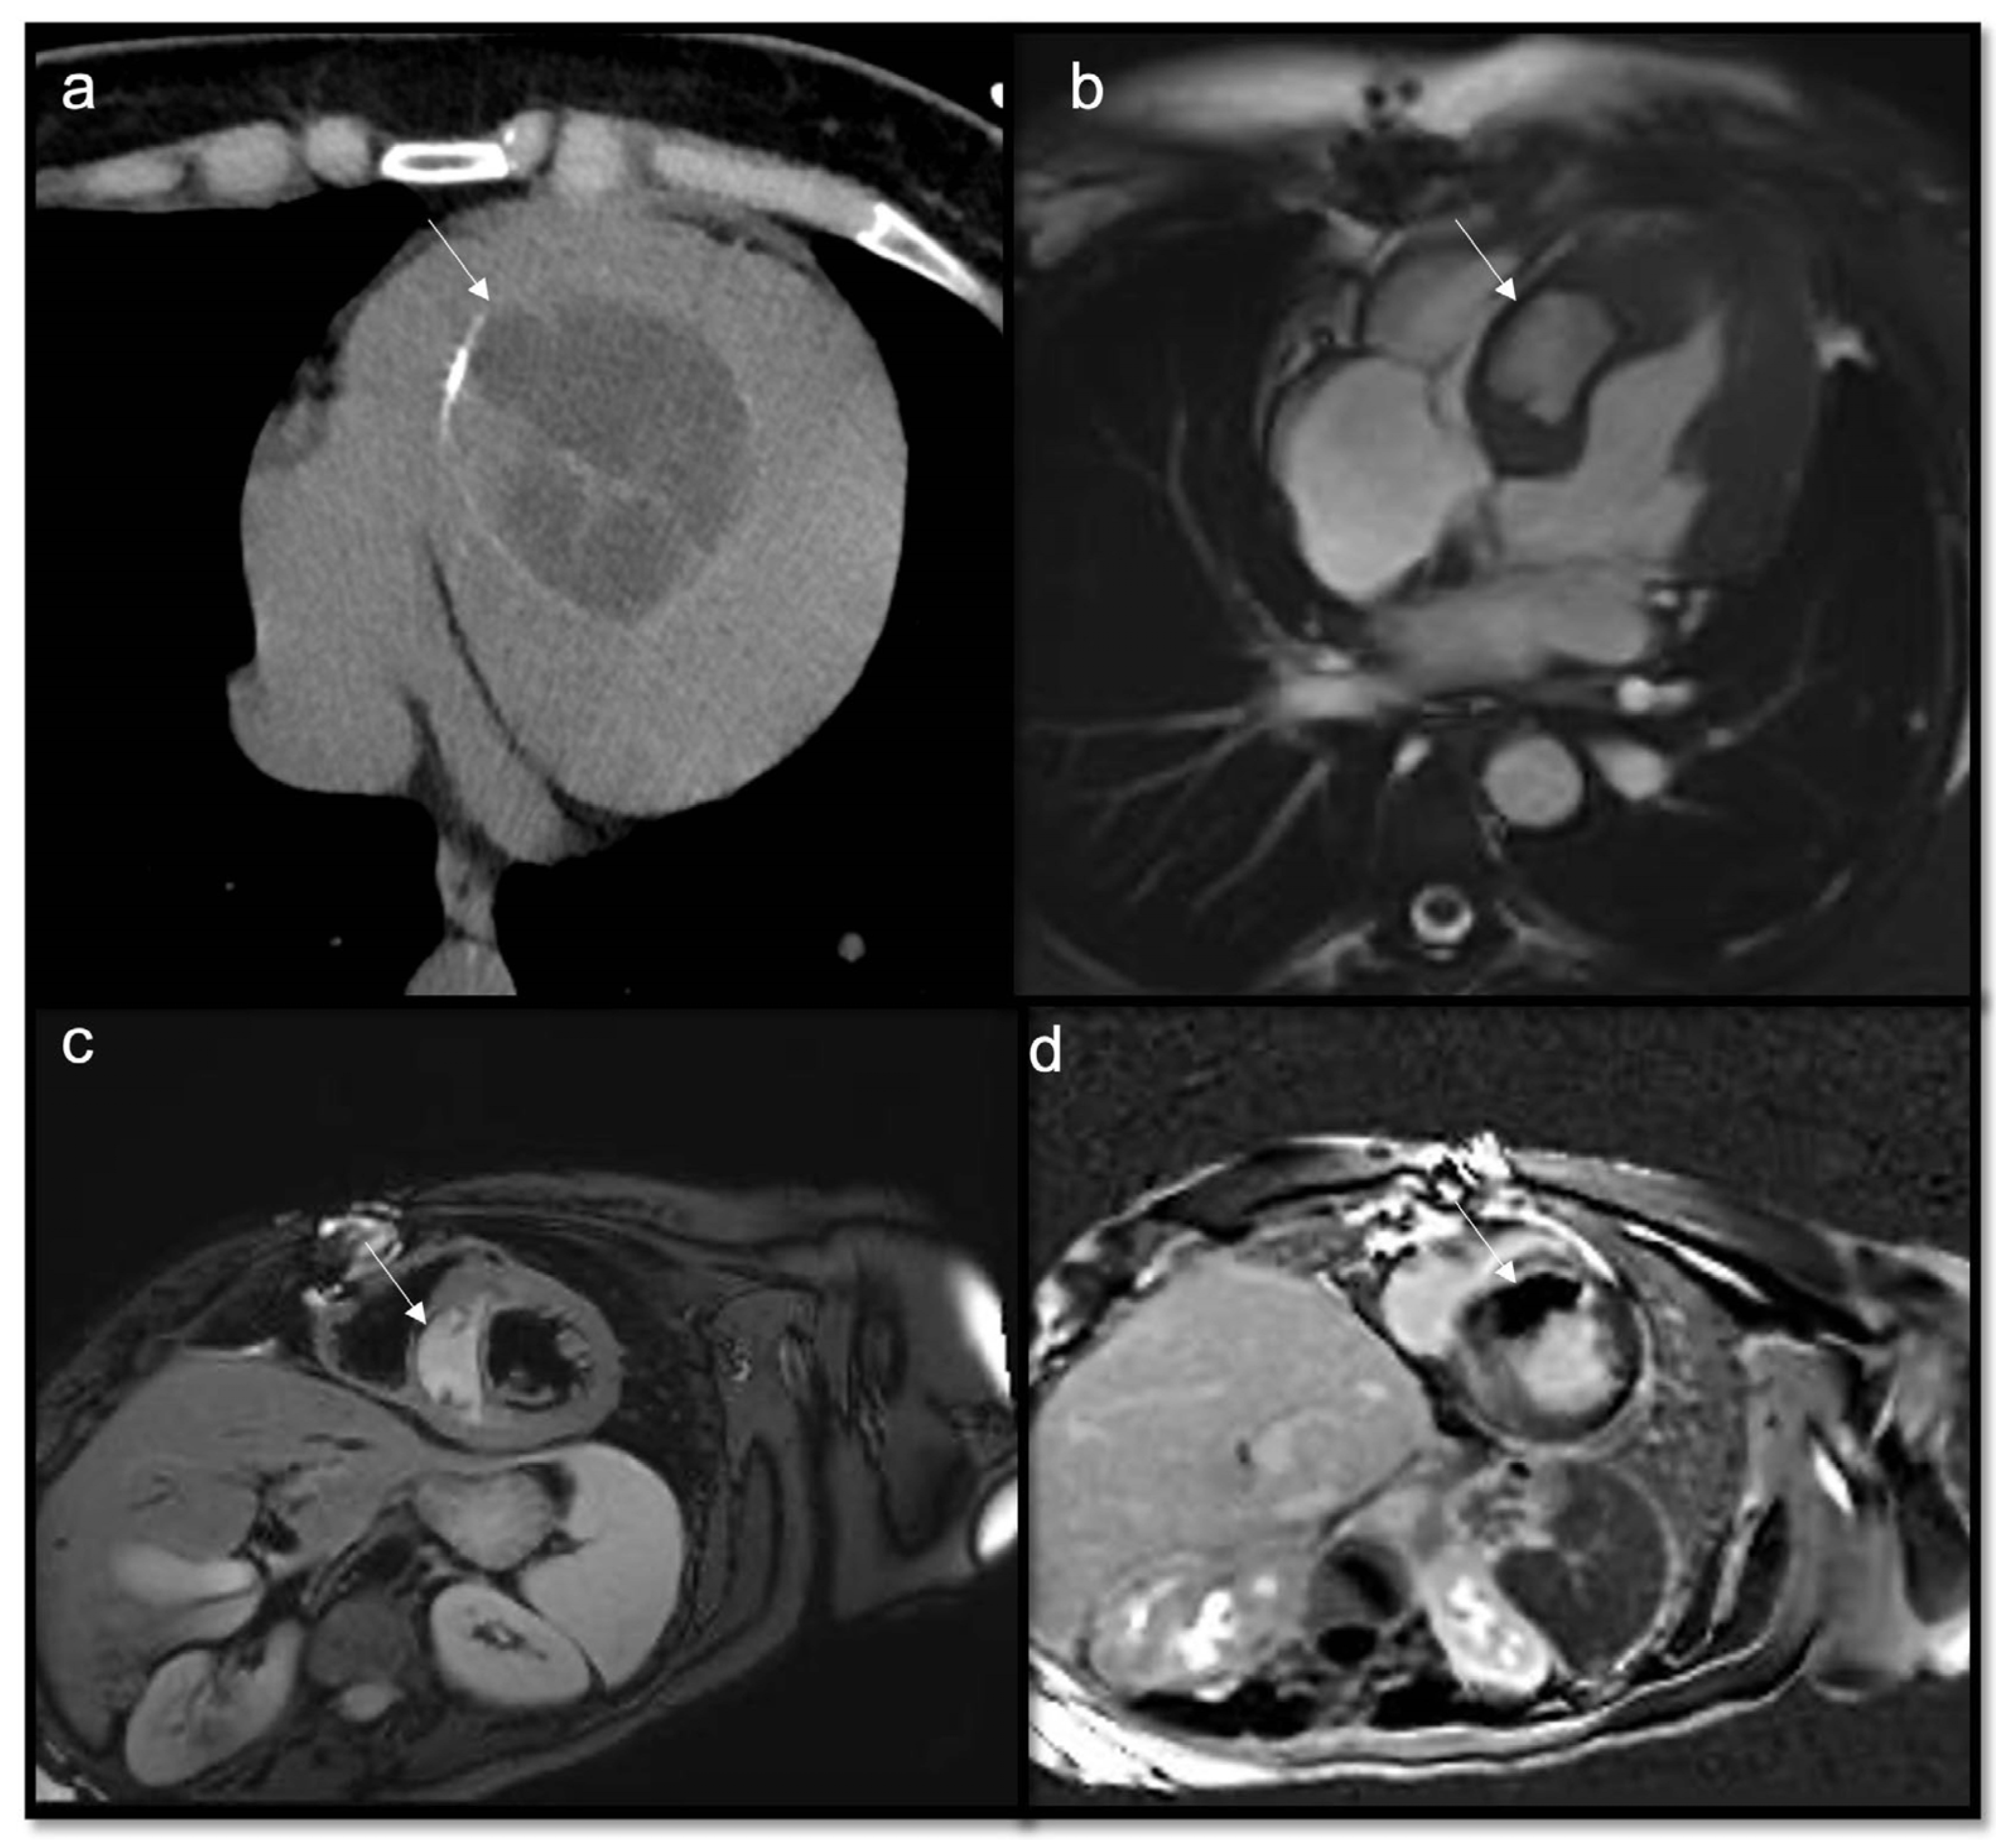

Figure 9.

Papillary fibroelastoma of the tricuspid valve (arrow) appears as a highly mobile, spherical pedunculate mass attached to the posterior tricuspid valve leaflet and on T1w images (a) it is homogeneous; no fatty content is found in T2w Fat Sat (b). LGE images demonstrate a hyperintense signal caused by fibroelastic tissue of the mass in 4CH and 2CH of the right ventricle (c,d). Approximately 80% occur concerning either the aortic or mitral valve, while tricuspid and pulmonary involvements are much rarer.